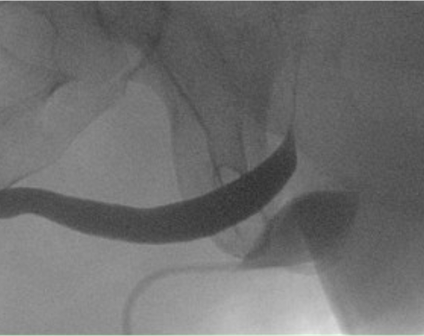

Einleitung: Die adjustierbare Schlinge ATOMS SSP (A.M.I. GmbH) wird bei Patienten mit Harninkontinenz nach Prostataeingriffen transobturatorisch implantiert und stellt eine Alternative zur fixen Schlinge/dem artifiziellen Sphinkter dar. Die Positionierung hängt dabei von unterschiedlichen Faktoren ab und erfolgt standardmäßig eher im distal bulbären/proximal penilen Harnröhrenbereich. Am Universitätsklinikum Münster wurde eine neue Technik entwickelt, die eine idealisierte Positionierung mit indirektem und direktem Support des Rhabdosphinkters verspricht (Abbildung 1 [Abb. 1] und 2 [Abb. 2]). Die proximale Implantation setzt sich aus 4 Einzelschritten zusammen: 1) Durchtrennen des Centrum tendineum; 2) mediodorsale Punktion des Foramen obturatorium; 3) tiefes submembranöses Ausleiten der Helixnadeln und 4) straffe Adaptation der Mesh-Arme, um das Kissen hinter den Bulbus urethrae zu kippen. Nach Publikation der erfolgreichen Anwendung in Einzelfällen bei anhaltender Inkontinenz nach Standard ATOMS SSP-Implantation sollen nun Ergebnisse einer größeren Kohorte auch bei primärer Implantation vorgestellt werden.

Abbildung 1

Abbildung 2